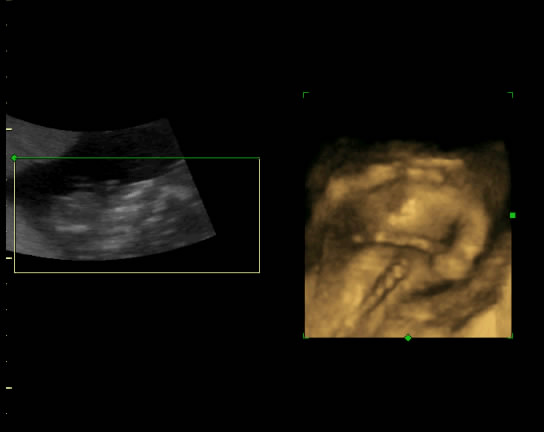

Ez a köldökzsinór dolog azért érdekes, mert a 18 héten volt egy 4D-s ultrahang kép és akkor a nyakán volt, azóta nem láttuk, hogy mi a helyzet, mert sima uh-n nem látszik.

juci: hidd el, hogy a sima uh-n nem látták, még szerencse, hogy voltunk egy uh konferencián és ott a 4D-n egyértelmű volt, képet teszek.

zsinór

Kép